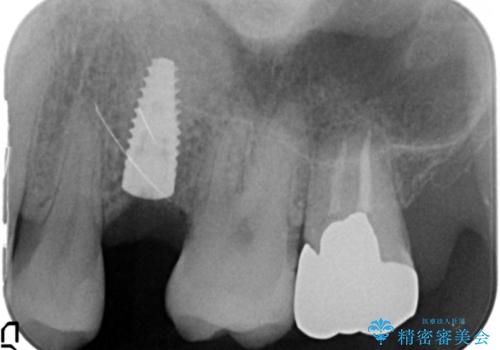

患者様のご希望により、抜歯後インプラント治療を行いました。

骨の厚みが不足していたため、インプラントの埋入と同時にソケットリフト(上顎骨に骨を増やす手術)を行いました。

インプラントの種類:ストローマン BLT